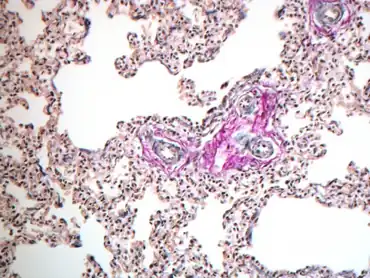

Pathophysiology

Typically, a fetus experiences pulmonary hypertension in utero since it is relying on the placenta for oxygen rather than its lungs. When the fetus is born, it is no longer attached to the placenta and must use the lungs to receive oxygen. To facilitate this change from fetus to newborn, the baby must change from a state of high PVR to low PVR, allowing for increased blood flow to circulate throughout the body.[3] This inability of the newborn to adapt to these changes is caused by various processes, such as:

- Normal vascular anatomy with functional vasoconstriction: This has a good prognosis, as it is reversible. Causes include hypoxia, meconium aspiration, and respiratory distress syndrome. Left untreated, this can lead to hypoxic respiratory failure (HRF).[1]

- Decreased diameter of pulmonary vessels with hypertrophy of vessel walls: This has a poor prognosis, as it is a fixed abnormality. Causes include post-term pregnancy, placental insufficiency, and NSAID use by the mother.

- Decreased size of pulmonary vascular bed: This has a poor prognosis, as it is a fixed abnormality. It is caused by space occupying lesions such as pleural effusions and diaphragmatic hernias.